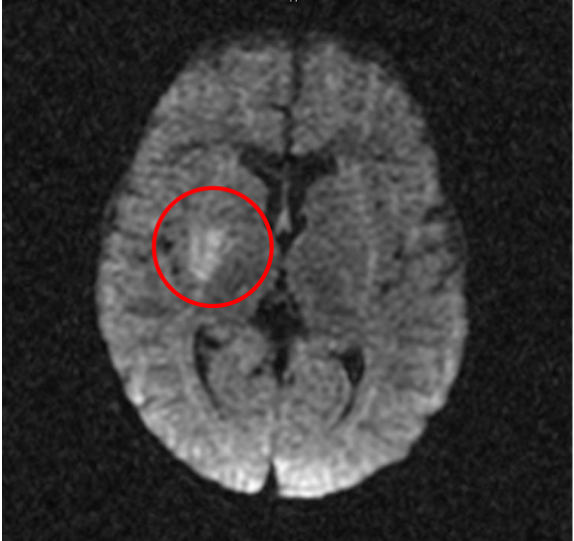

Alla risonanza non vengono evidenziate formazioni espansive, ma viene rilevata �un'area ischemica in sede lenticolare, nella porzione media della corona radiata e alla giunzione testa-corpo del nucleo caudato di destra�. L'angio-RM eseguita a completamento diagnostico documenta una settoriale occlusione dell'apice del sifone carotideo di destra, con riduzione di calibro della carotide interna a monte che risulta filiforme nel suo tratto intracranico; le arterie cerebrali anteriore e media di destra risultano riperfuse attraverso un vaso comunicante. (Figura 1 e Figura 2). Al fine di escludere condizioni cardiologiche predisponenti, viene eseguita anche una ecocardiogramma che risulta nella norma.

Figura 1. Area ischemica in sede lenticolare, nella porzione media della corona radiata e alla giunzione testa-corpo del nucleo caudato di destra.